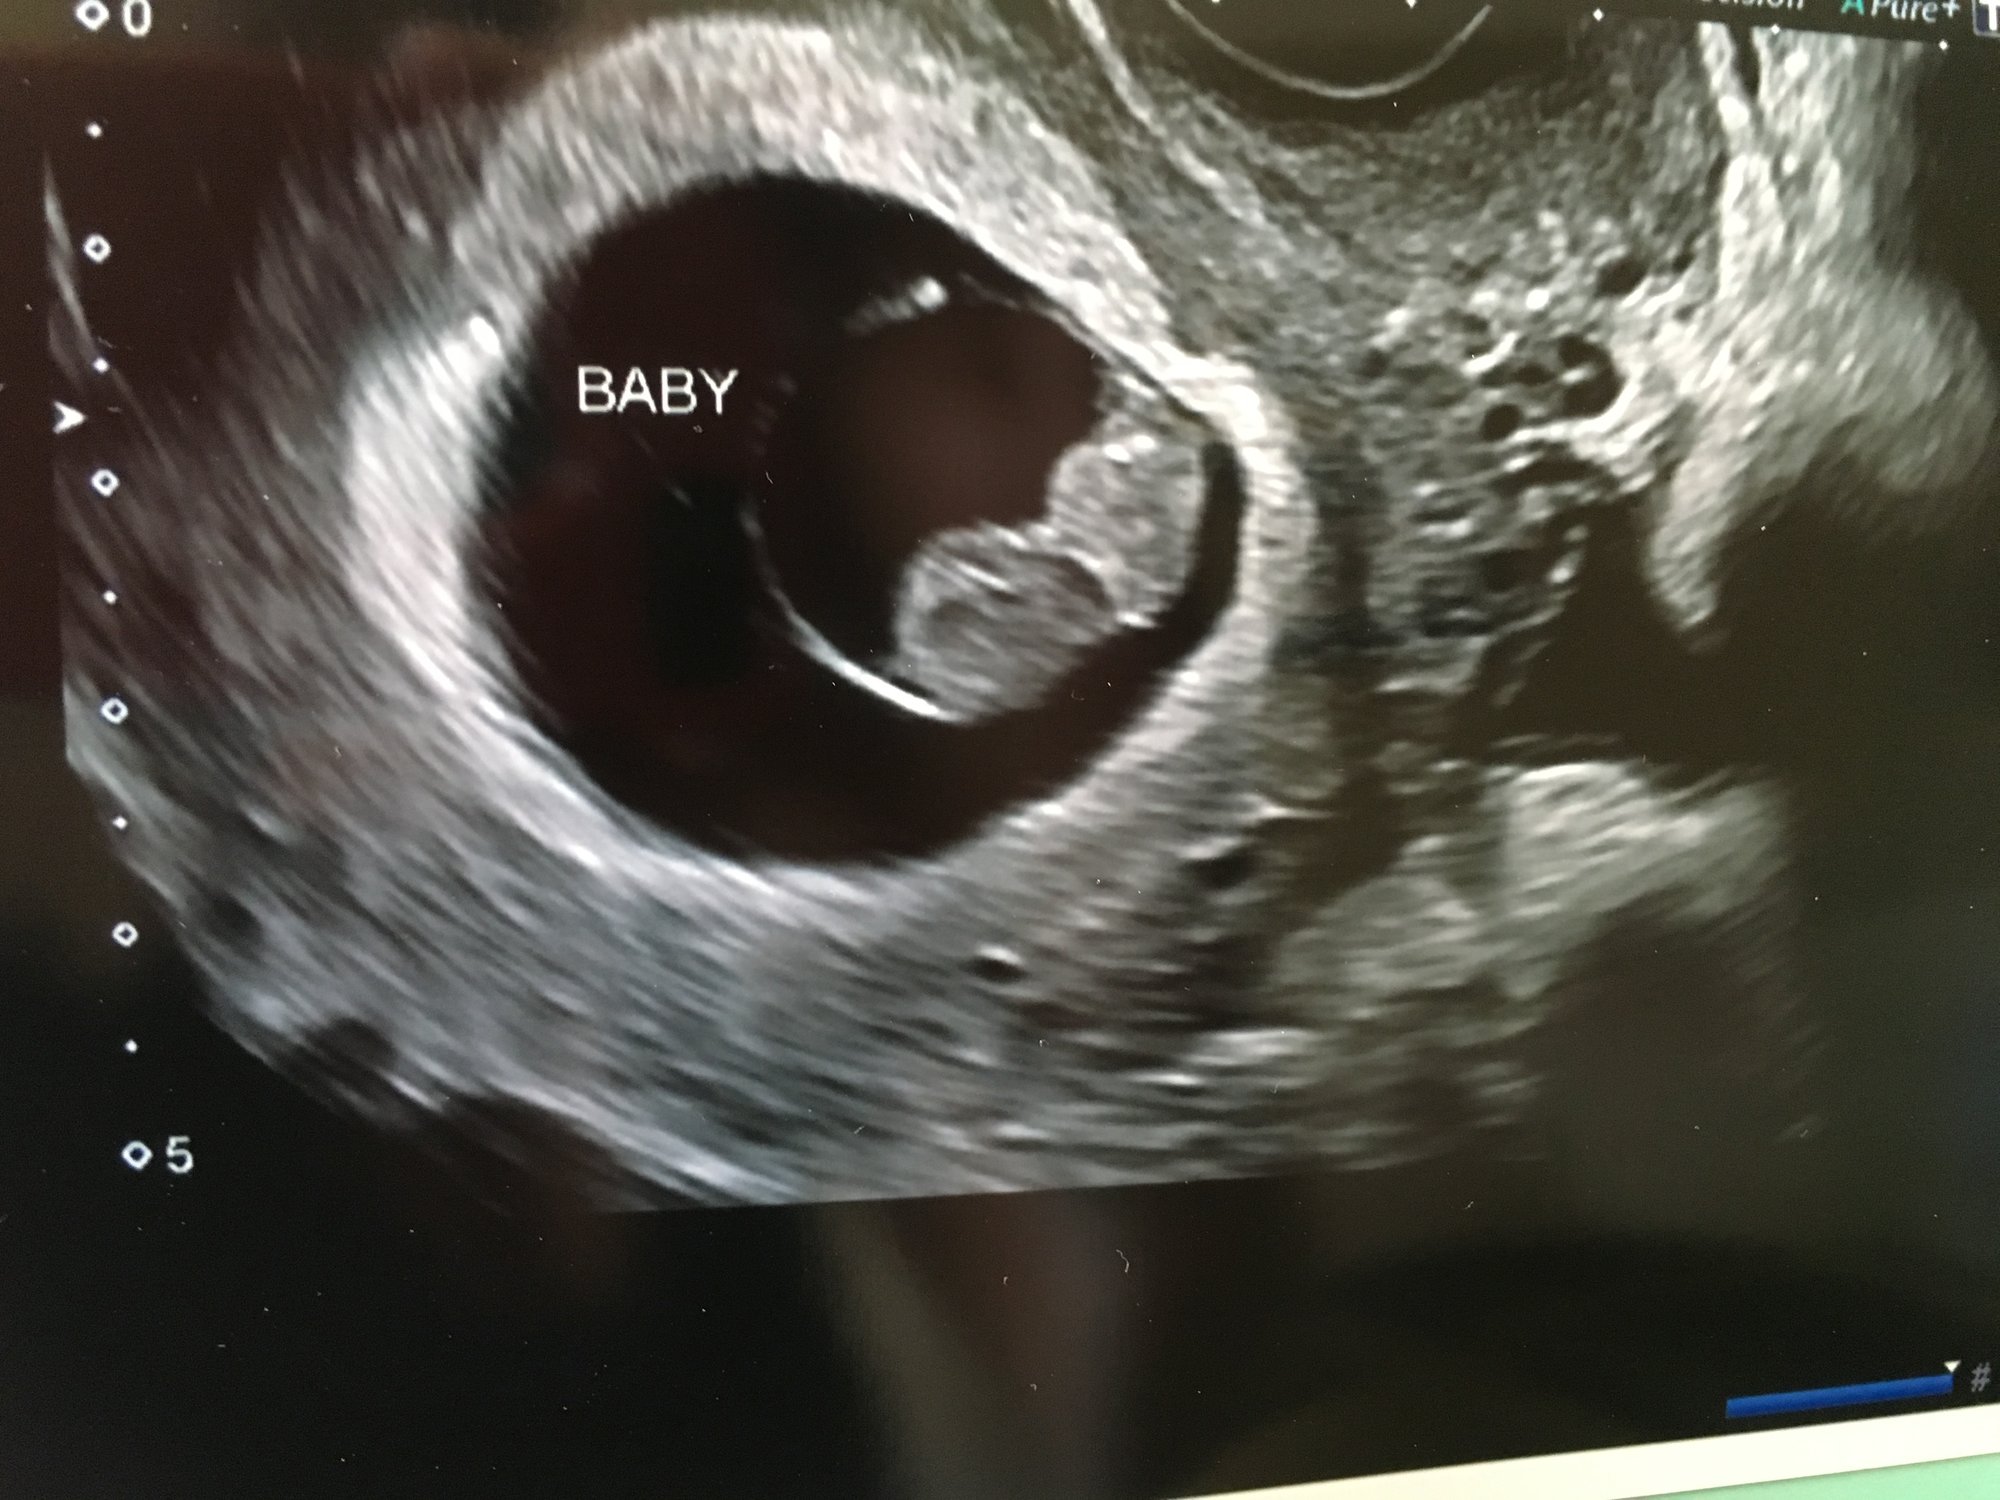

• Finally got to have our first ultrasound today!!! I'm at 9 weeks and 2 days, and the baby measured exactly that. Heart rate was 161 bpm, and we got to watch the heart beat on the monitor. The baby was bouncing and wiggling on the screen it was adorable. Did anyone else cry at their first ultrasound?!